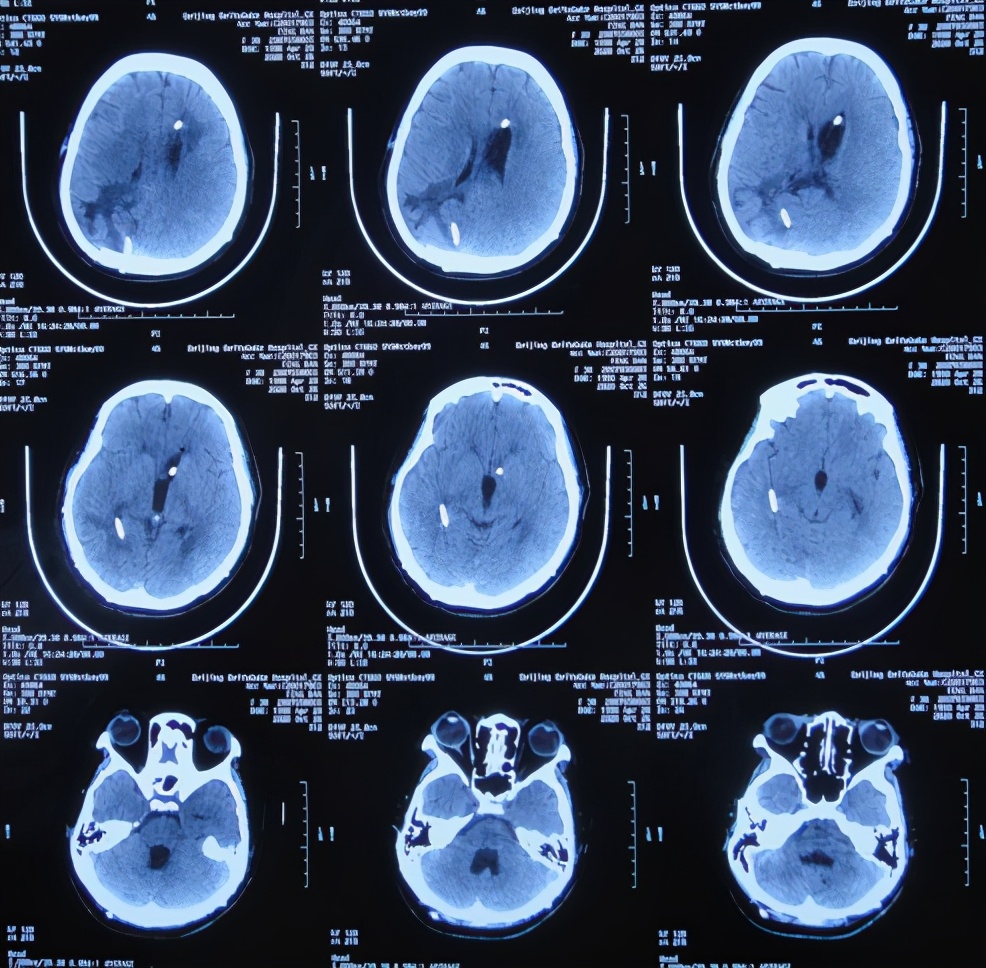

入院当天复查头颅CT示脑血管畸形术后改变,脑积水引流术后,脑膨出,右侧颞枕顶叶及左侧额叶脑水肿,严重脑室粘连( 图-17 );胸部CT示双肺肺炎(片子丢失)。

图-17: 2020年7月5日头颅CT

入院次日即2020年7月6日,进行了颞角外引流术,术后当天复查头颅CT示脑室内有2根管( 图-18 ), 脑脊液细菌培养示肺炎克雷伯菌(仍是外院开颅术后14天时查出的细菌,说明之前的细菌一直并未彻底消灭)。

图-18: 2020年7月6日头颅CT